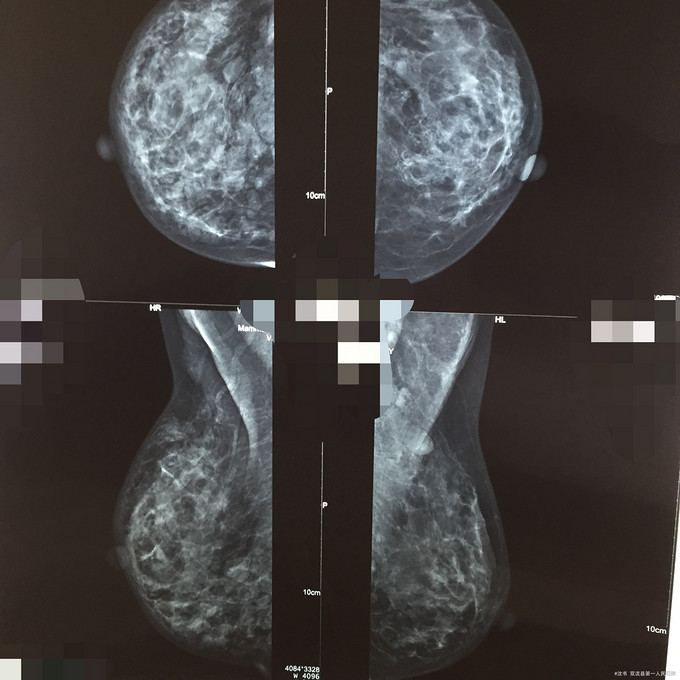

双乳隆乳术后右乳多发结节

查体:双对称,右乳中央区、7-8点韧硬结节,左乳头中央三孔浑浊液少许,右乳头无溢液,余(-)。 辅查:双乳彩超:双乳及右腋残存假体?双乳X线:双乳后间隙结构紊乱:术后改变?

诊断:1、双乳多发小结节:假体?2、双乳后间隙结构紊乱:术后改变? 处理:密切随访:每半年复查双乳彩超,每2年复查双乳X线。

患者采用不正规地注射隆乳术,注射物在体外无法被完全降解,引起周围组织异物反应,影响双乳影像学检查,以及掩盖双乳新发病灶。而且手术也无法完全取干净这些注射物,可谓是后患无穷。